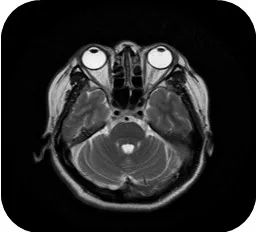

颅脑MRI:双侧额叶脑白质内脱髓鞘改变;双侧上颌窦炎;右侧乳突炎。